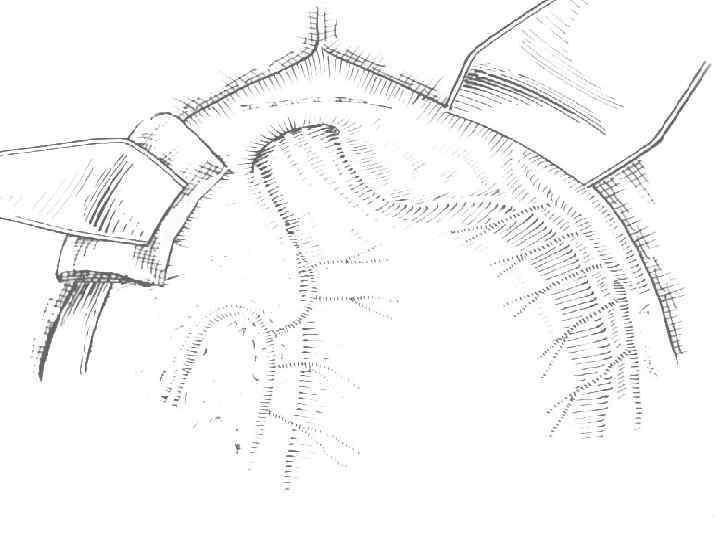

Ромбовидная пилоропластика. В виде ромба рассечена передняя порция пилорического жома и гастроанастомоз

Наложение первого ряда швов по Пирогову-Матешуку